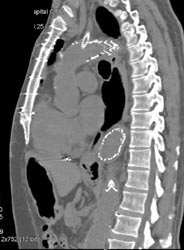

Av Shunt in Liver